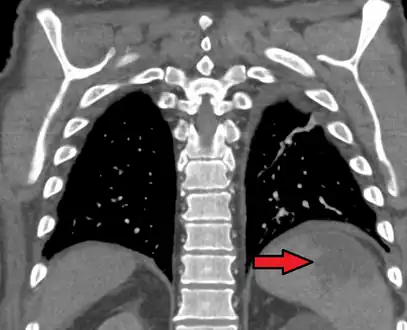

a, b) Splenic infarction.

An abdominal CT scan is the most commonly used modality to confirm the diagnosis,[3] although abdominal ultrasound can also contribute.[16][17][18]